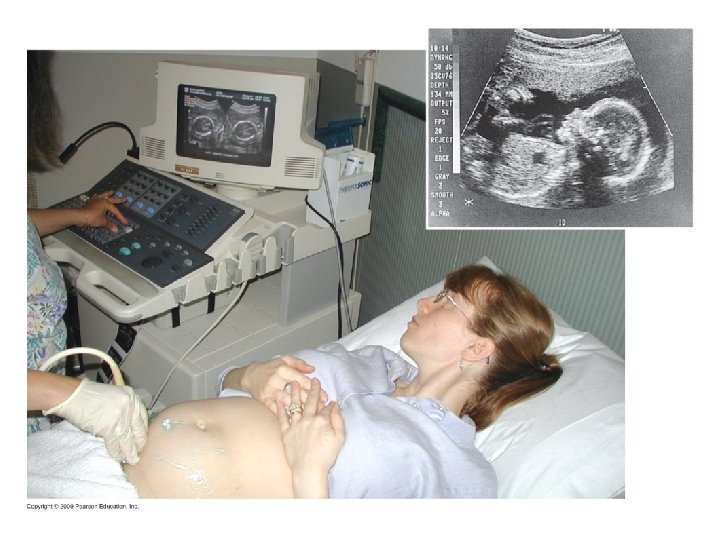

9. 10 CONNECTION: New technologies can provide insight into one’s genetic legacy Genetic testing of parents Fetal testing: biochemical and karyotype analyses – Amniocentesis – Chorionic villus sampling Maternal blood test Fetal imaging – Ultrasound – Fetoscopy Newborn screening Copyright © 2009 Pearson Education, Inc. Video: Ultrasound of Human Fetus

Chorionic villus sampling (CVS) Amniocentesis Needle inserted Ultrasound through abdomen to monitor extract amniotic fluid Ultrasound monitor Fetus Placenta Uterus Chorionic villi Cervix Suction tube inserted through cervix to extract tissue from chorionic villi Cervix Uterus Amniotic fluid Fetal cells Centrifugation Fetal cells Several weeks Biochemical tests Karyotyping Several hours